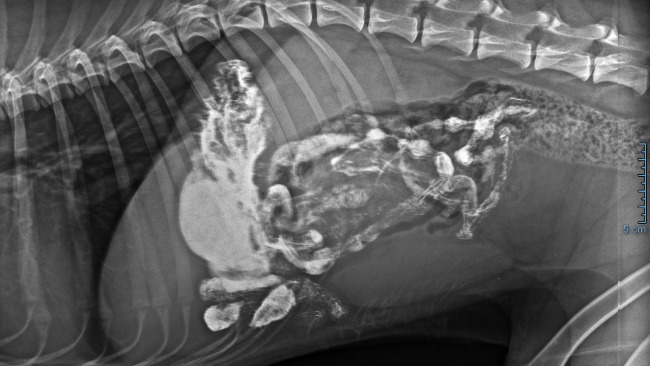

Znowu! Znowu coś się dzieje! Znowu jakaś choroba 😞 Oskarek poczuł się źle końcem grudnia. Jest w trakcie diagnostyki bo niewiadomo co się Mu dzieje a dzieje się uwierzcie mi z psiaka aktywnego, radosnego zrobił się psiakiem apatycznym, sennym nie chcę Mu się nic😞 Boli Go boli go brzuch boli go gęba, chudnie w oczach jest słaby 😭Lekarze obstawiają że to jelita. Dostał antybiotyk i serie zastrzyków, kroplówki.